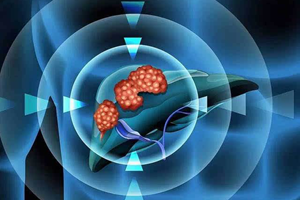

新评分系统可预测慢乙肝抗病毒治疗期间的肝癌风险

新评分系统可预测慢乙肝抗病毒治疗期间的肝癌风险

CAMD评分可以预测CHB患者口服抗病毒药物治疗期间的HCC风险。

CAMD评分可以预测CHB患者口服抗病毒药物治疗期间的HCC风险。关键字:评分系统,预测,风险

新评分系统可预测慢乙肝抗病毒治疗期间的肝癌风险

CAMD评分可以预测CHB患者口服抗病毒药物治疗期间的HCC风险。关键字:评分系统,预测,风险 伤肝药物繁多 如何避免入坑